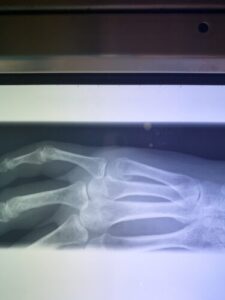

さわやか千葉県民プラザ(指骨骨折)